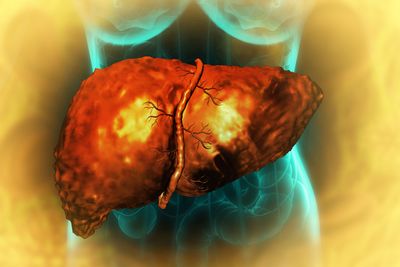

The rest of this article is behind a paywall. Please sign in or subscribe to access the full content.Liver fibrosis is the buildup of excessive scar tissue in the liver as a result of chronic injury. Fibrosis is one of the later stages of chronic liver disease and typically develops slowly, after years of damage to the liver from things like infection, autoimmune conditions, and alcohol use.

If left untreated, liver fibrosis can progress to cirrhosis, which can then give rise to liver cancer or other potentially fatal complications. A 2025 study estimated that 3.3 percent of people worldwide have advanced fibrosis.

One promising target is a subset of cells called hepatic stellate cells (HSCs). During liver injury, extra HSCs get activated and overproduce collagen and fibrous tissue, which builds up over time and hardens the liver, disrupting its function.